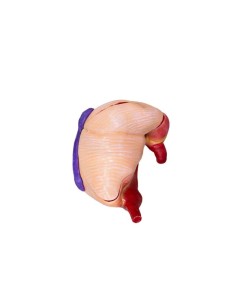

- Chien : nous proposons une sélection de simulateurs pour chiens, idéaux pour pratiquer un large éventail de procédures diagnostiques et thérapeutiques sur cette espèce animale commune.

- Chat : les simulateurs pour chats permettent de s'entraîner aux procédures vétérinaires spécifiques à cette espèce, offrant ainsi une formation complète et précise aux professionnels.

- Cheval : pour les professionnels travaillant avec des équidés, nous proposons des simulateurs précis et réalistes pour pratiquer des procédures diagnostiques, thérapeutiques et chirurgicales sur les chevaux.

- Souris : les simulateurs de souris sont essentiels pour la formation pratique à la recherche biomédicale et aux soins des animaux de laboratoire, car ils offrent une formation complète et compétente au personnel vétérinaire.

- Vache : pour ceux qui travaillent avec des animaux de ferme, nous proposons des simulateurs de vache pour pratiquer des procédures diagnostiques et thérapeutiques spécifiques à l'espèce.

Chaque catégorie propose une sélection de simulateurs de haute qualité, fabriqués à partir de matériaux durables et réalistes, afin de garantir une expérience de formation pratique efficace et précise.